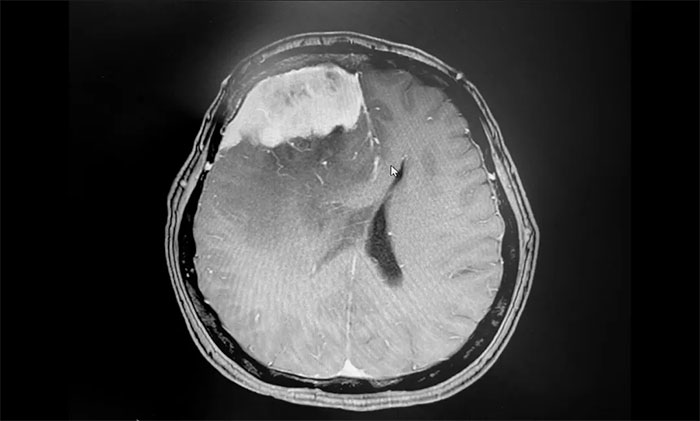

手術(shù)順利完成后,患者生命體征平穩(wěn),安返監(jiān)護(hù)病房。留取病理標(biāo)本送檢,確定為腦膜上皮型腦膜瘤(WHO I級(jí)),為良性腫瘤。

▲ 病理分析確定為腦膜上皮型腦膜瘤(WHO I級(jí))